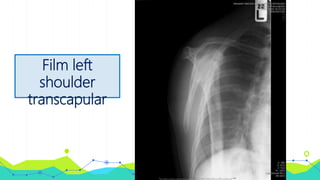

• Film left shoulder transcapular

Film left

shoulder

transcapular